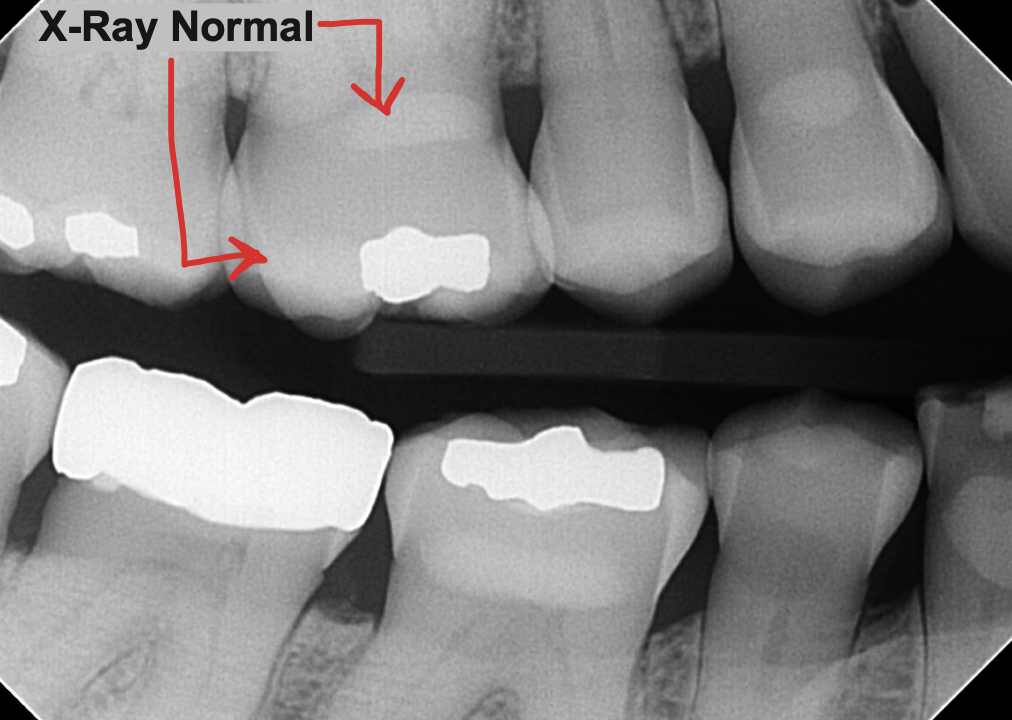

👀 Step 1: Pre-Op Evaluation

Before removing the tooth, we assessed bone health and root position with detailed imaging. In this case, the tooth had a prior root canal and a cavity on the back side, which caused the crown to loosen and eventually fall off. This tooth could not be saved by a new crown, so it needed to be extracted to prevent risk of infection and further damage of surrounding tissue. After reviewing alternative options, this patient is planning on a future dental implant to restore the site.

Images:

X Ray of tooth #18 Prior to Extraction

✅ Purpose: understand root formation, nerve anatomy, and ensure the socket walls are intact for grafting.